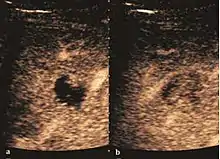

Liver cyst

Hydatid liver cyst. Diagnostic criteria are the presence of membranes and sediment inside.